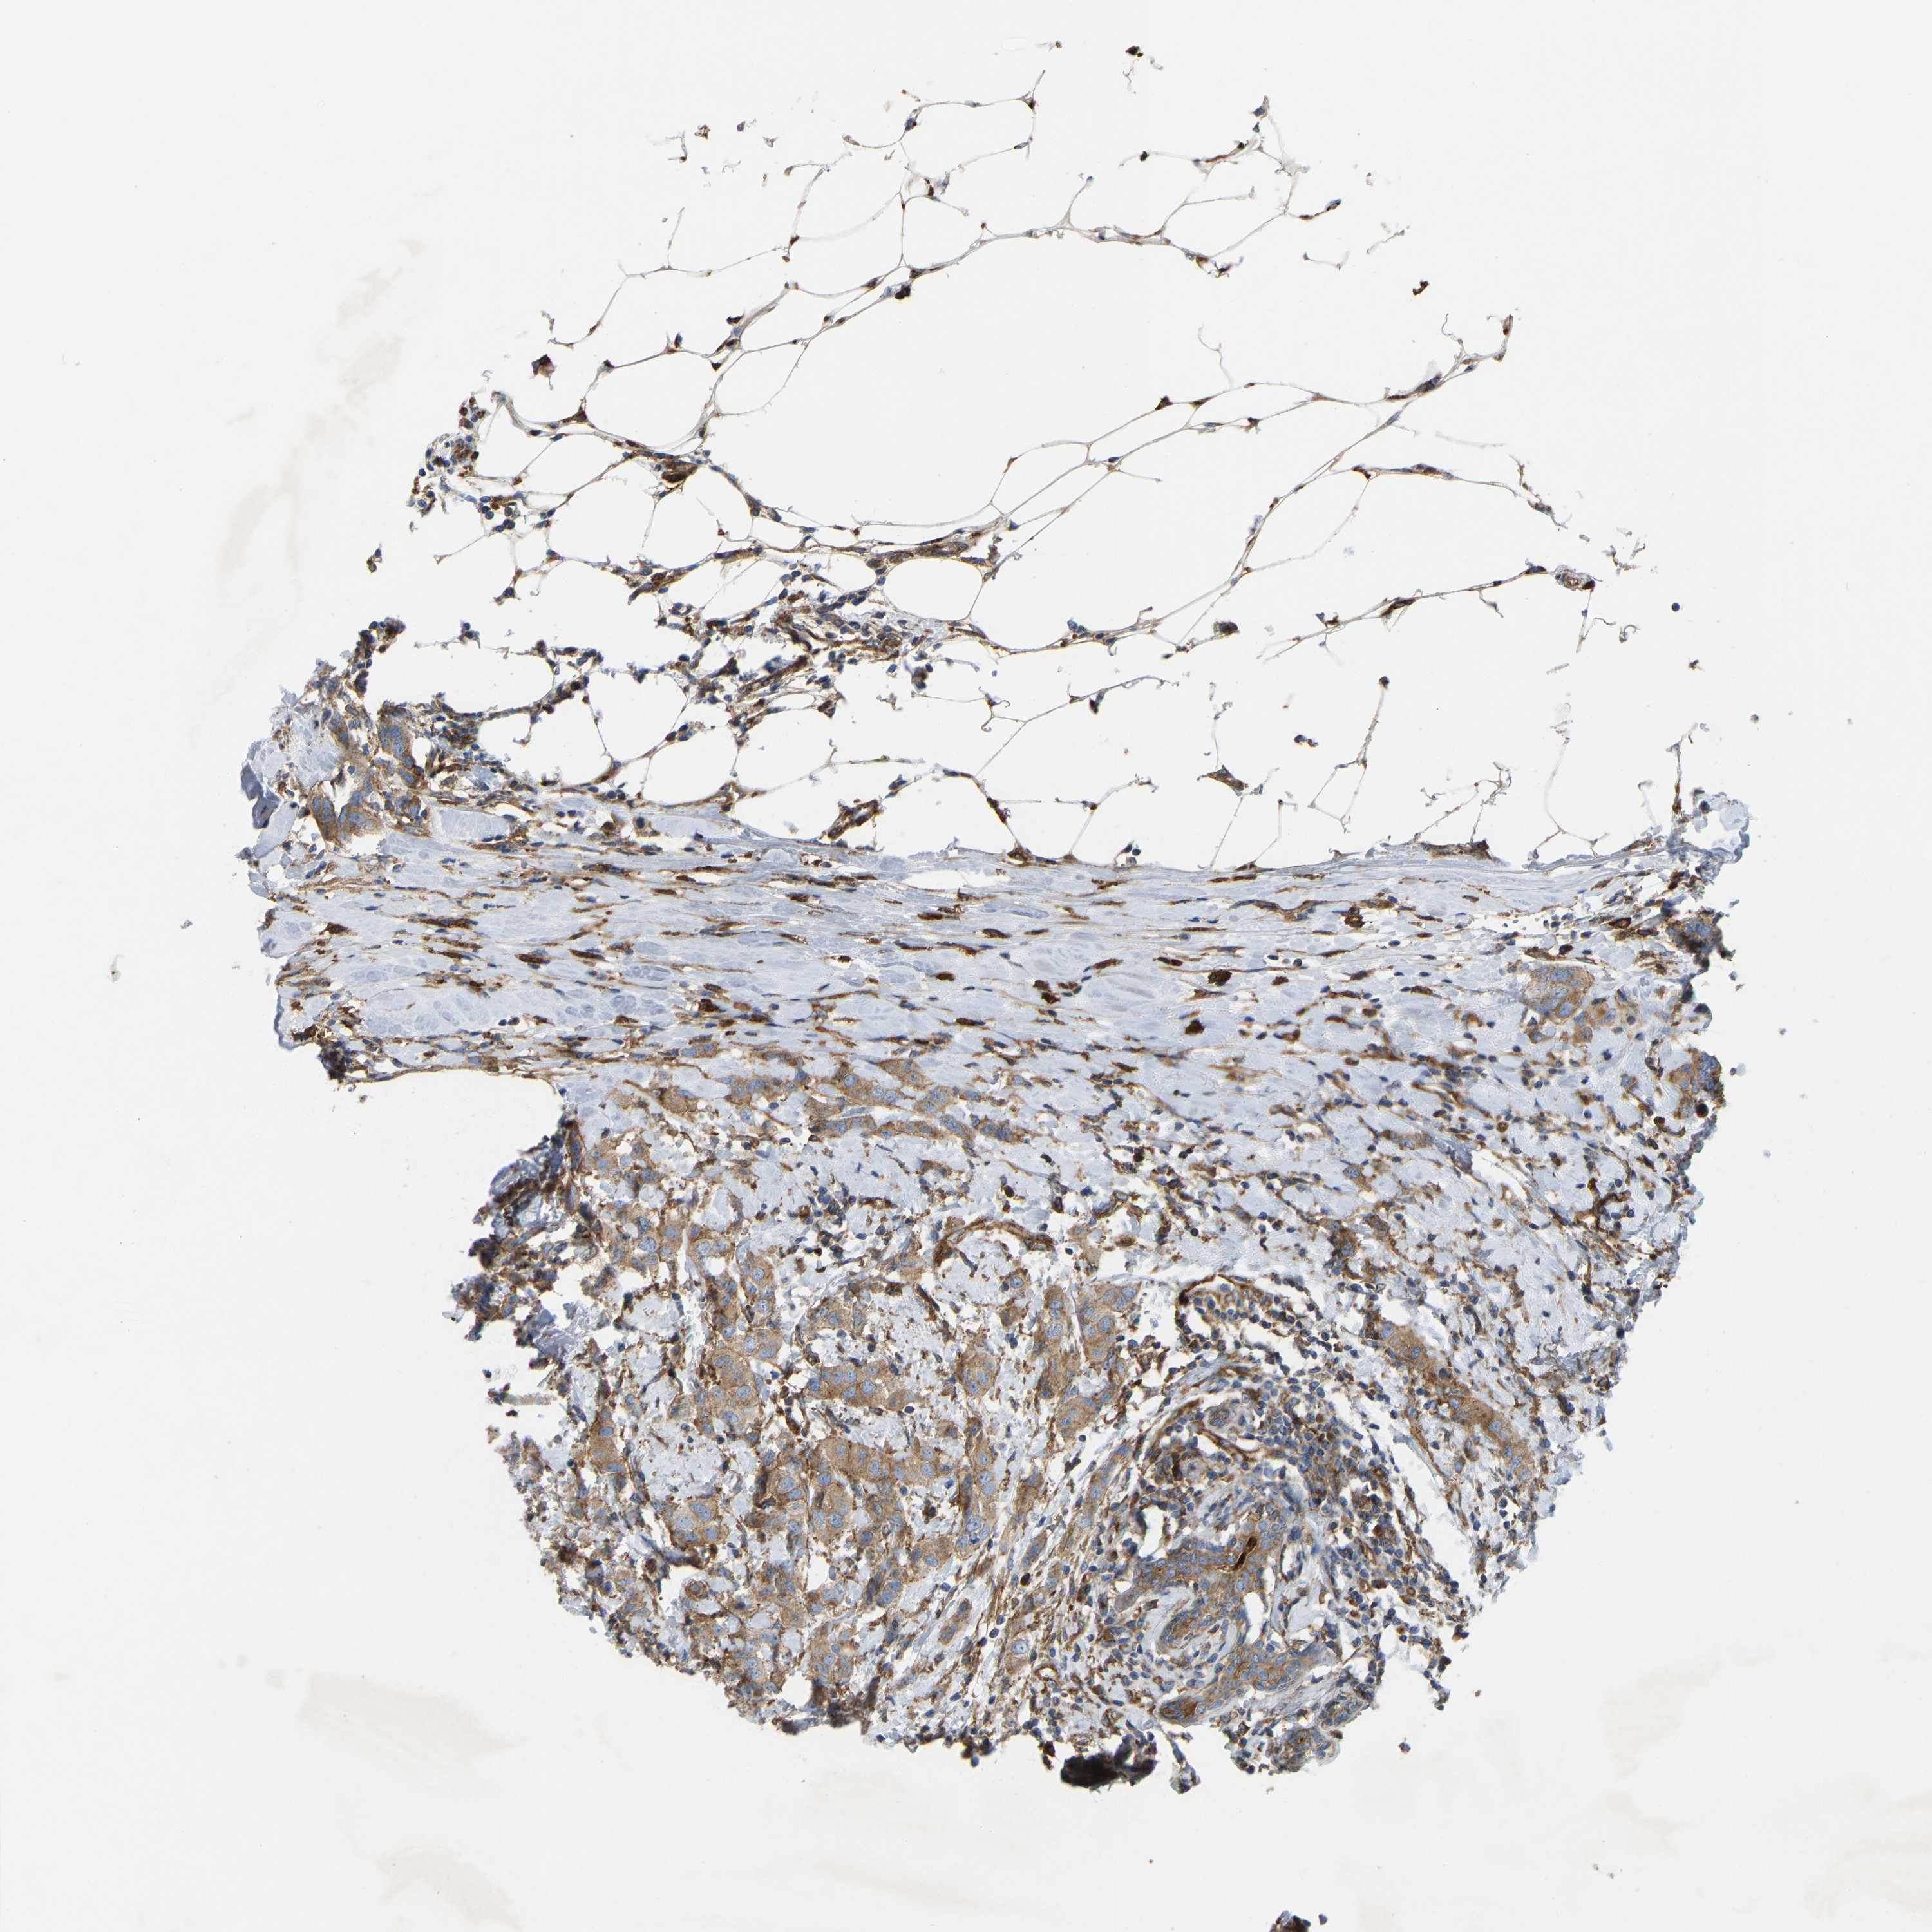

CANCER BREAST CANCER Show tissue menu

BRCA TCGA BRCA VALIDATION PROTEIN EXPRESSION